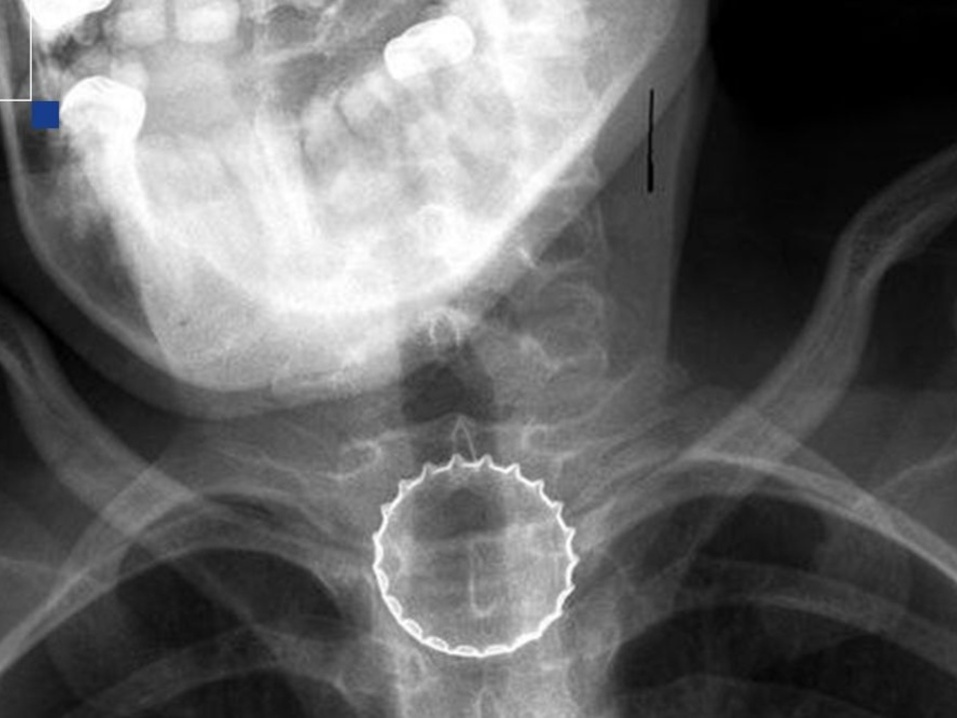

В Челябинске подростку удалось спасти жизнь благодаря операции по удалению застрявшей в пищеводе металлической крышки от бутылки.

В Челябинске произошло случайное происшествие, которое могло стать фатальным для 16-летнего подростка. Во время игры с металлической крышкой от бутылки, мальчик неосторожно подбросил ее и она застряла в его пищеводе, полностью перекрывая его. Пострадавший сразу же обратился за помощью в экстренное приемное отделение Челябинской областной клинической больницы (ЧОДКБ).

Ситуация требовала немедленного вмешательства, и врачи отправили мальчика на операционный стол. Благодаря использованию видеоэндоскопического оборудования врачам удалось без повреждения внутренних органов достать крышку. Операция прошла успешно, и мальчику провели контрольное обследование, подтвердив, что его слизистая оболочка не пострадала.